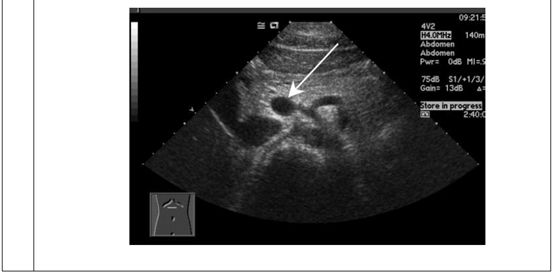

69.下圖為肝臟之橫切面,箭號所指為肝臟的那一個部位?

(A)左葉

(B)尾葉

(C)右葉

(D)左葉外側節

統計: A(161), B(1568), C(95), D(207), E(0) #1635415